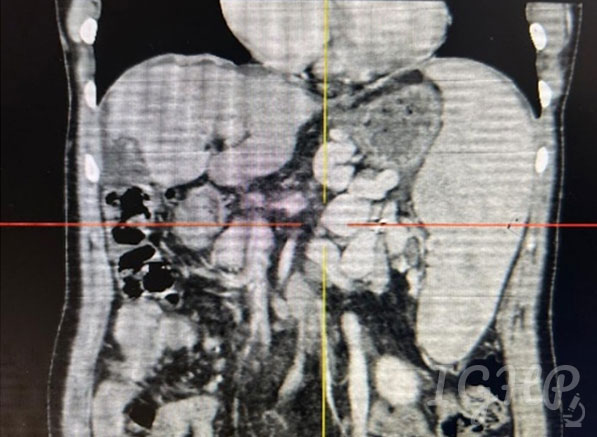

CECT Abdomen-

Cirrhotic liver with splenomegaly with dilated splenic vein and multiple dilated torturous collaterals in peripancreatic splenic hilar peri gastric and lienorenal region. Portal vein 10mm, No ascites.